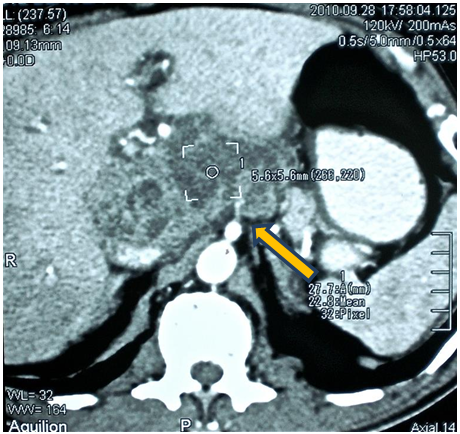

Figure 2 Computerized axial tomography with double contrast. Yellow arrow points retroperitoneal collection image of heterogeneous appearance.

Abdominal ultrasound Figure 1 showed a cystic-looking image with low-level, ecolucent images inside, 20x13mm in diameter, while in double-contrast computed tomography (Figure 2) observed a lesion occupying retrogastric space, towards the transcavity of the epiplons, adjacent to the pancreatic head, hypodense, with poorly defined edges, with attenuation coefficients within the solid and liquid range, 5.6x5.6cm in diameter. In the upper digestive endoscopy a rounded lesion was evident that pushed the posterior face of the heart. A puncture was performed and a purulent liquid was drained from which sample was taken for cytology and culture, which proved to be an inflammatory exudate with abundant polymorphonuclear and basophilic bacterial aggregates (Actynomices). The patient is managed with medical treatment and antibiotic therapy for several weeks under the presumptive diagnosis of complicated pancreatic head tumor with intra-abdominal collection; however, in the persistence of the symptomatology, a diagnostic laparoscopy was planned. During the surgical act when addressing the transcavity of the epiplons, a foreign body was found that came from the stomach (Figure 3), perforating its posterior wall and making contact with the head of the pancreas conditioning a plastron (Figure 4). The foreign body was removed and after a wash and aspiration of the cavity, the surgery was completed.